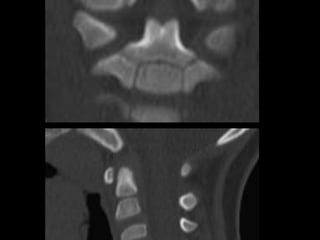

69 year old man with C2

fracture

Admitted for CHF and while

hospitalized was walking to

the bathroom at night and

fell on to head lacerating

forehead. Staff responded

to his calls for help and

immediately ordered a

cervical CT due to

complaints of new neck

pain

69 year oldman with C2 fracture Admitted for CHF and while hospitalized was walking to the bathroom at night and fell on to head lacerating forehead. Staff responded to his calls for help and immediately ordered a cervical CT due to complaints of new neck pain PMH: COPD, CHF, anxiety/dep, liver cirrhosis, cognitive decline, pulmonary HTN, SH: retired lives in group home